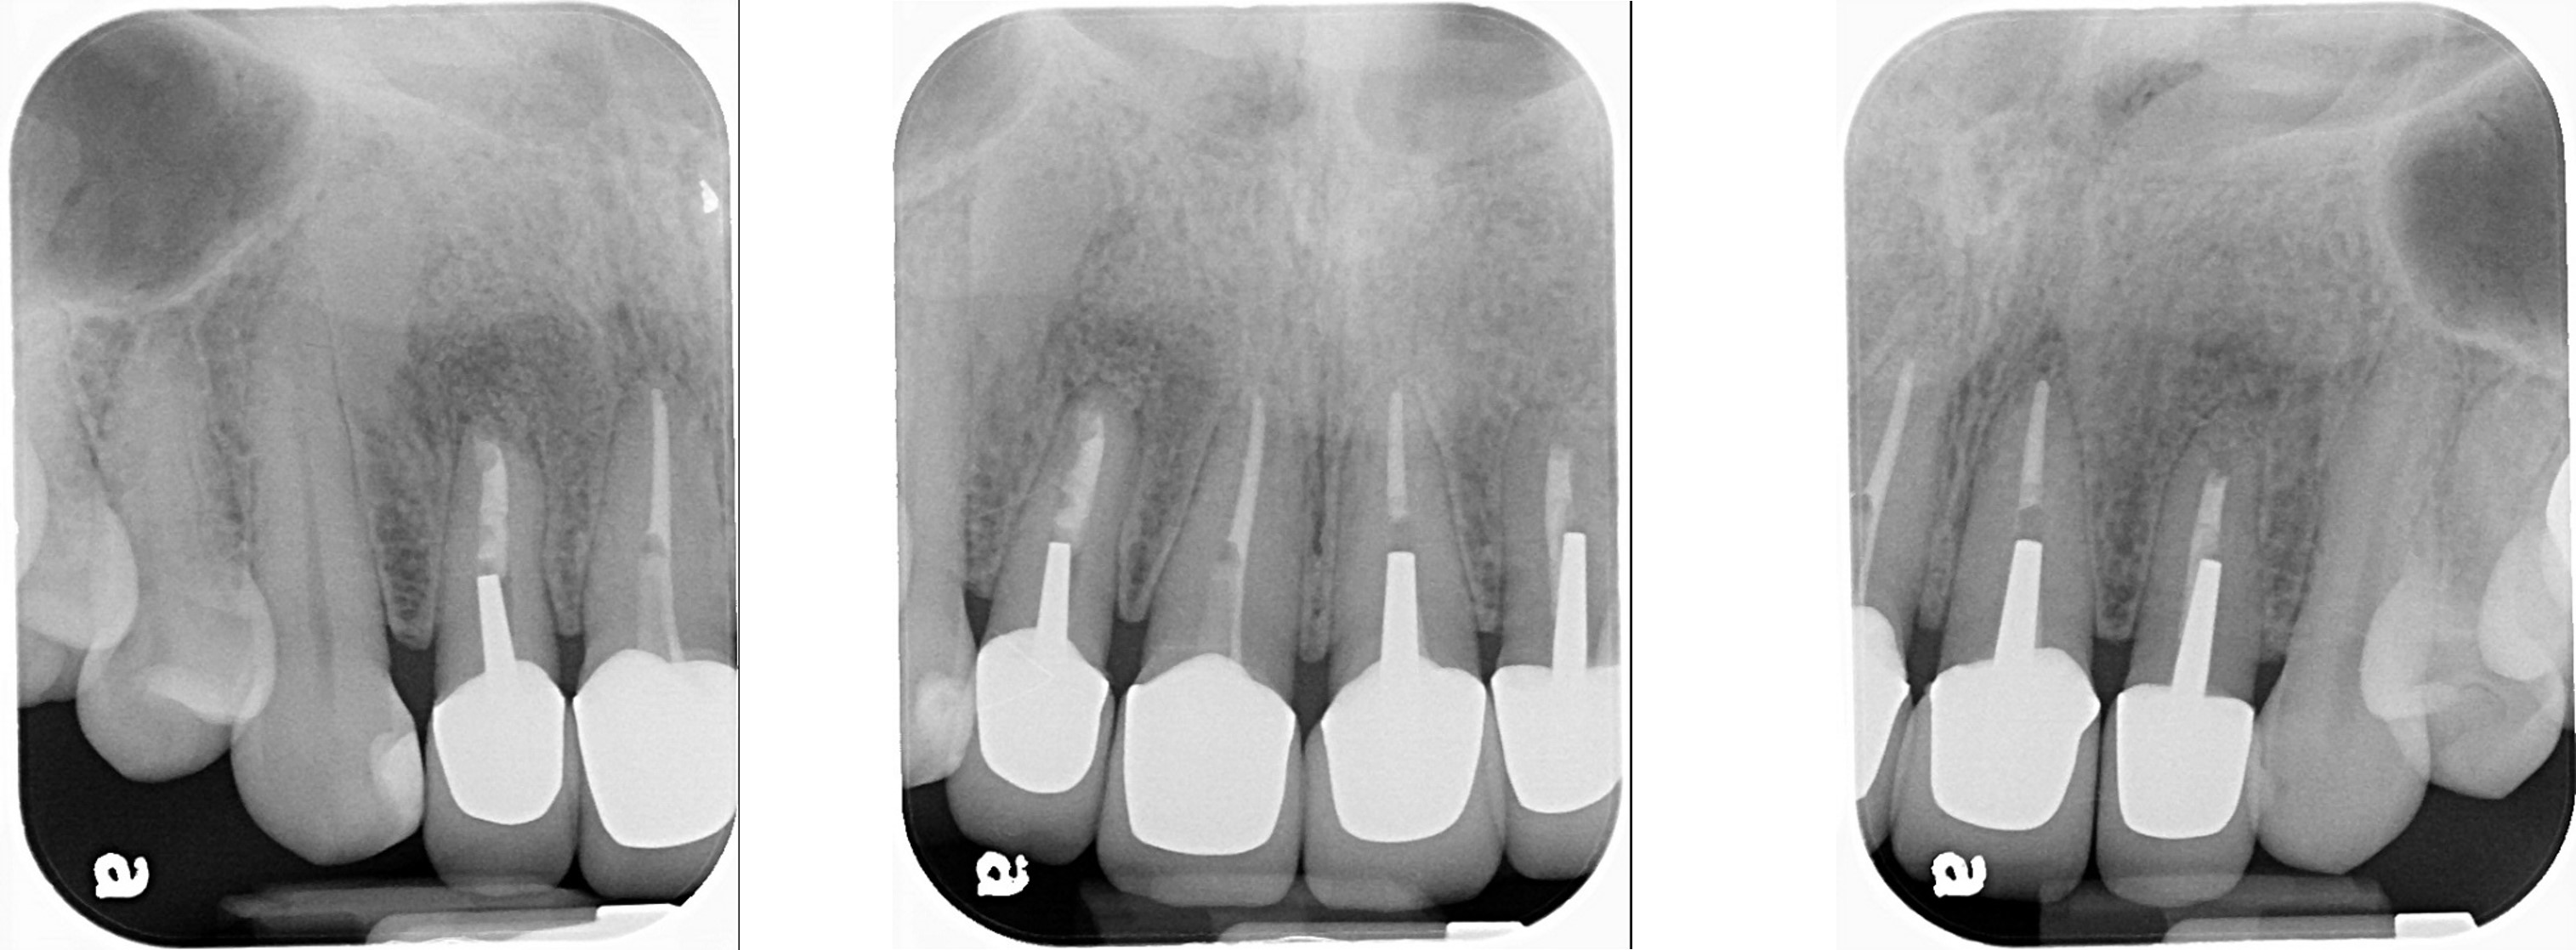

治療前,前牙根管治療不完全

根管治療6個月後,仍有根尖病變

前牙顯微根尖手術

6個月後病變逐漸恢復

再6個月後,病變更消失

根尖病變消失